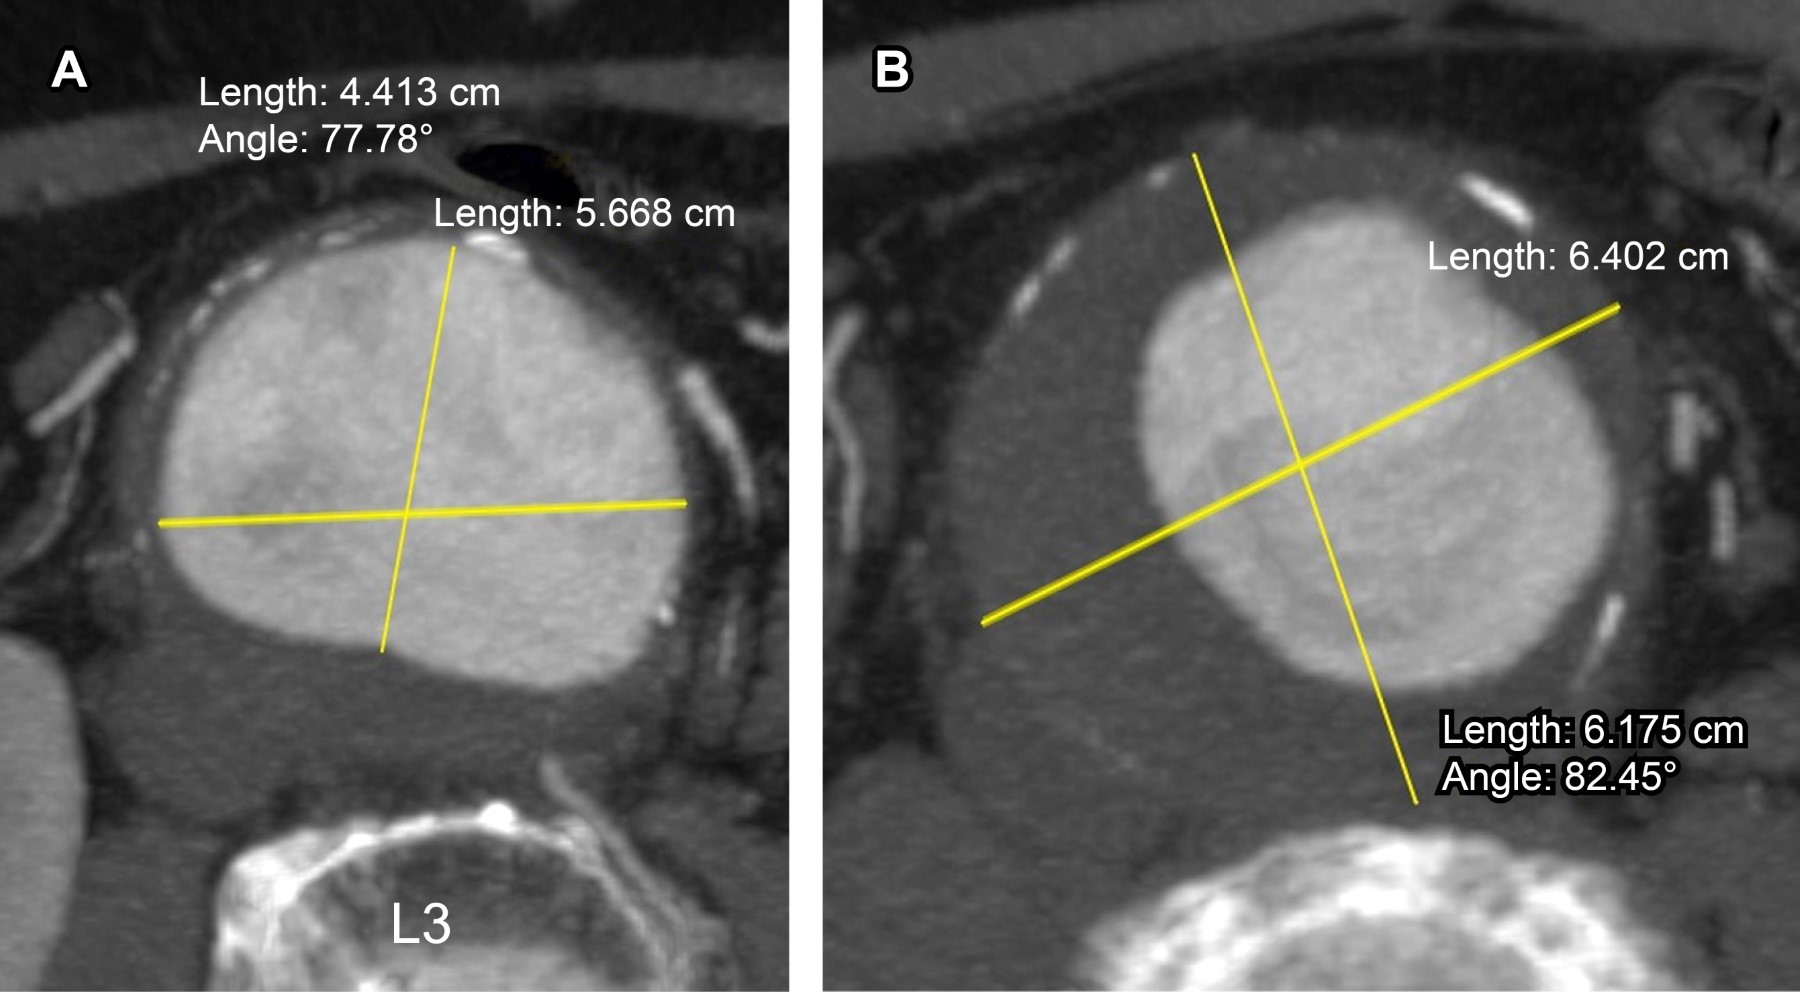

Abdominal Aortic Aneurysm (AAA) is a potentially fatal pathology, present in 2-4% of the population over 50 years of age. Angiotomography (CTA) allows localization of AAA, determines its length, the involvement of visceral branches and flow characteristics. Currently CTA is used to plan endovascular treatment. Treatment depends on the size and location of the aneurysm, age, renal function and other conditions. Aneurysms smaller than five centimeters in diameter are usually monitored by ultrasound or CT every six to 12 months. Surgical treatment is recommended in aneurysms with a diameter greater than 5 centimeters; the risk of rupture is four times higher in women. As a cultural fact of interest, the physicist Albert Einstein died of AAA rupture on April 18, 1955.

Figure 1